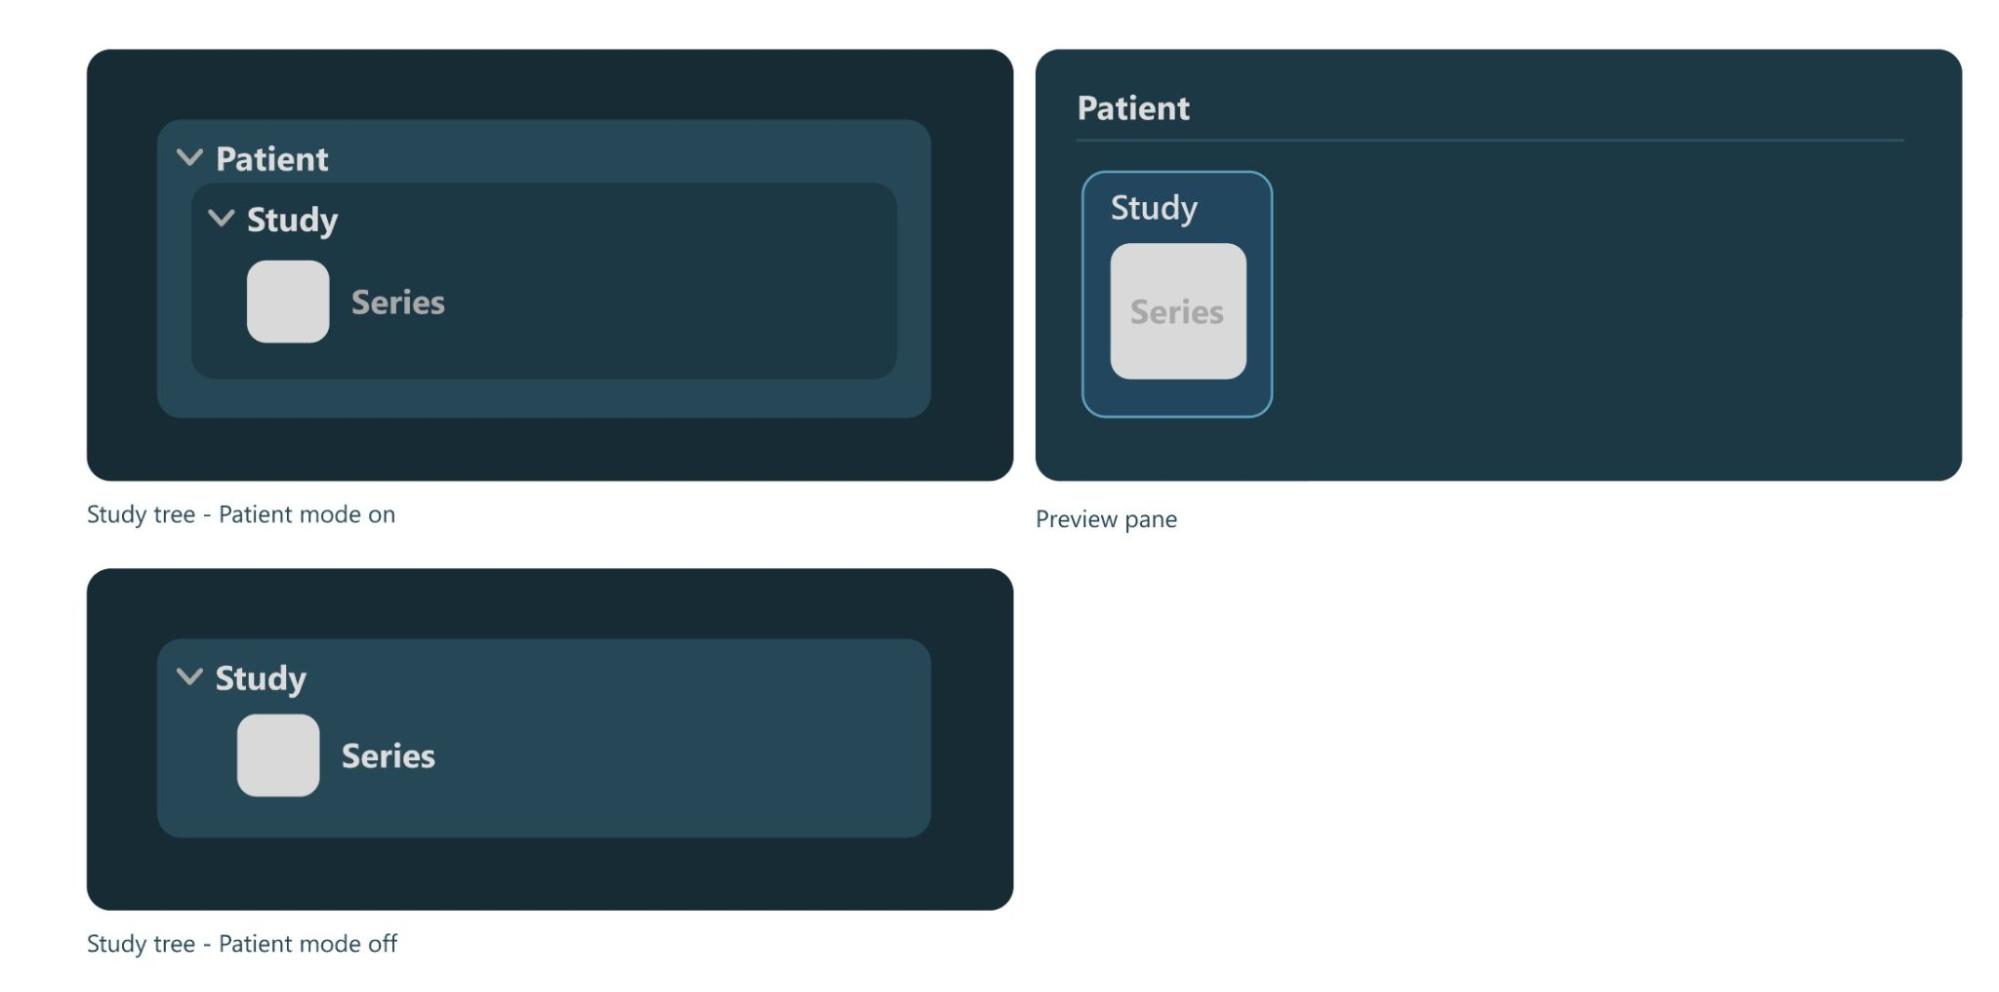

Patient Mode¶

Patient Mode enabled and toggled on. When the patiend mode is active, the studies in the Study List are grouped into patients, where multiple studies can be related to one patient. To only display studies in the Study List, toggle the patient mode off.Patient Mode option in the settings, which means that the Study List will always be represented with studies only.Refresh Study Browser¶